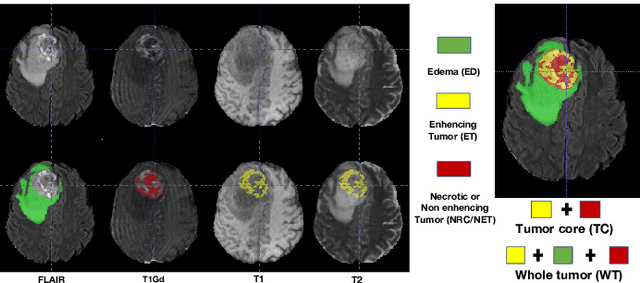

Abstract:Single-modality medical images generally do not contain enough information to reach an accurate and reliable diagnosis. For this reason, physicians generally diagnose diseases based on multimodal medical images such as, e.g., PET/CT. The effective fusion of multimodal information is essential to reach a reliable decision and explain how the decision is made as well. In this paper, we propose a fusion framework for multimodal medical image segmentation based on deep learning and the Dempster-Shafer theory of evidence. In this framework, the reliability of each single modality image when segmenting different objects is taken into account by a contextual discounting operation. The discounted pieces of evidence from each modality are then combined by Dempster's rule to reach a final decision. Experimental results with a PET-CT dataset with lymphomas and a multi-MRI dataset with brain tumors show that our method outperforms the state-of-the-art methods in accuracy and reliability.

Abstract:As information sources are usually imperfect, it is necessary to take into account their reliability in multi-source information fusion tasks. In this paper, we propose a new deep framework allowing us to merge multi-MR image segmentation results using the formalism of Dempster-Shafer theory while taking into account the reliability of different modalities relative to different classes. The framework is composed of an encoder-decoder feature extraction module, an evidential segmentation module that computes a belief function at each voxel for each modality, and a multi-modality evidence fusion module, which assigns a vector of discount rates to each modality evidence and combines the discounted evidence using Dempster's rule. The whole framework is trained by minimizing a new loss function based on a discounted Dice index to increase segmentation accuracy and reliability. The method was evaluated on the BraTs 2021 database of 1251 patients with brain tumors. Quantitative and qualitative results show that our method outperforms the state of the art, and implements an effective new idea for merging multi-information within deep neural networks.